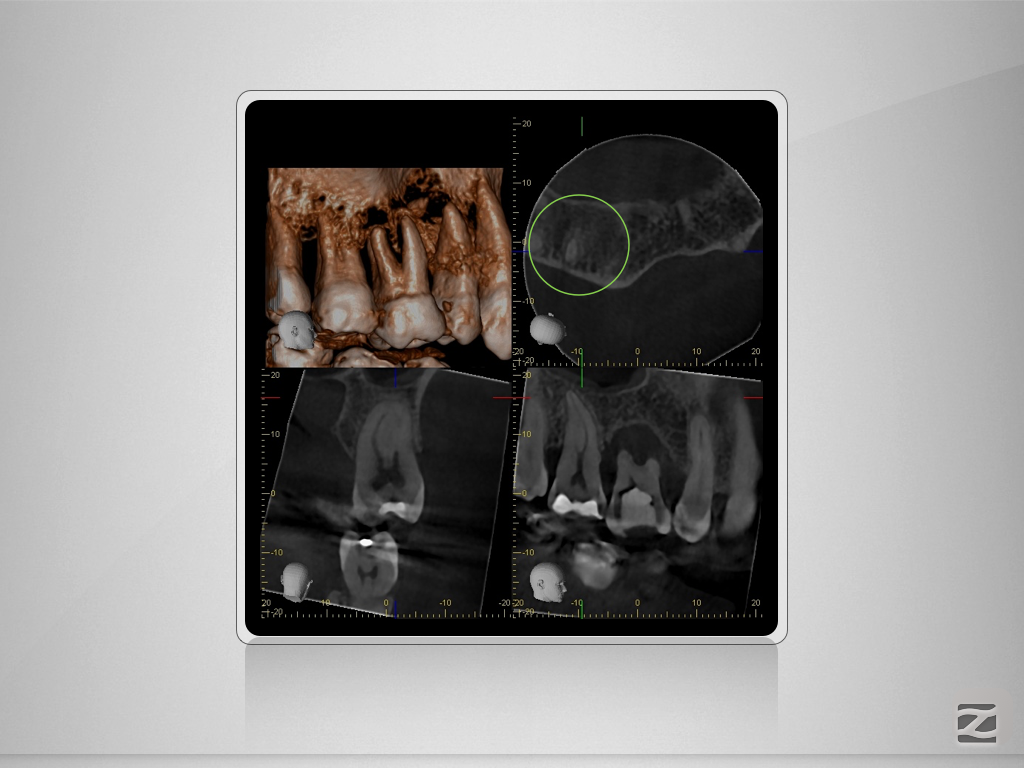

17D.011

Gewusst, wo’s lang geht.